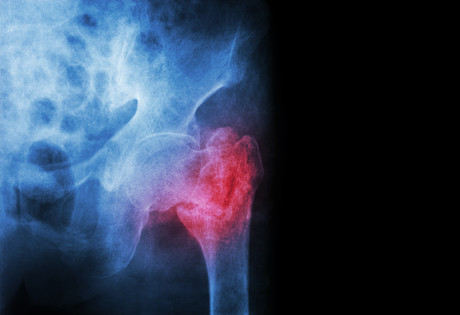

According to Dato’s Dr Joon-Kiong Lee, an orthopaedic surgeon from Malaysia, MJA Insight co-author and Asia Pacific Fragility Fracture Alliance Co-Chair, a fragility fracture, which currently occurs every three seconds across the globe,3 compromises quality of life and puts the affected individual at twice the risk for further fracture and loss of independence.4

“Fragility fractures, which commonly affect the hip, spine and wrist,5 are crippling to the lives of patients, their carers, families and communities alike.6 They also pose a significant resource and cost burden on health systems and economies, equating to an average 19% of GDP per capita.7

“Given our global population is rapidly ageing, with a projected 310% increase in hip fractures for men and a 240% increase in hip fractures for women by 2050,8 these alarming statistics demonstrate the need for systematic management of fragility fractures,” said Dr Lee. “The Asia Pacific Fragility Fracture Alliance will act as a catalyst for systematic change, by driving policy, increasing awareness, and influencing political and professional frameworks across the region.”